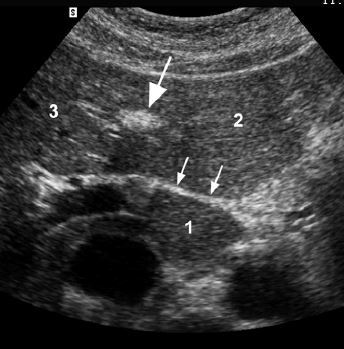

1. caudate lobe

2. segment II/III

3. segment IV

• large arrow - ligament teres

• small arrow - ligamentum venosum